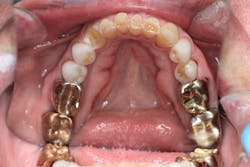

Radiographically, the first thing I noticed were the tabletopped occlusal surfaces (figures 1 and 2). Clinically, the same was evident, along with generalized wear facets on the posterior teeth (figures 3 and 4). The bite was deep (figures 5 and 6), and the lower anterior teeth had been worn down to half their original size. There were new ceramic crowns on nos. 21, 28, and 29. I also noted that there was an occlusal stop/resin on no. 13, but there was no significant effect on his occlusion as it was even on the right and left sides.